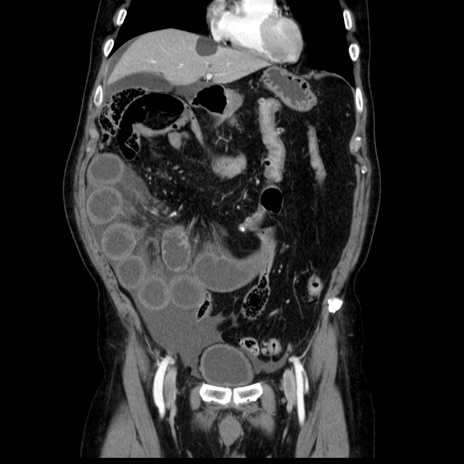

症例30(冠状断像)

【症例】80歳代男性

【主訴】臍周囲痛

【現病歴】約6時間前から臍下部痛が出現。次第に腹部膨隆・背部痛も生じてきたため来院。背部痛の場所は変化しない。

【既往歴】腎盂腎炎

【身体所見】意識清明、BT 36.3℃、BP  131/87mmHg、P 87bpm、SpO2 100%(RA)、臍周囲自発痛・圧痛あり、反跳痛なし、自発痛部位に一致して板状硬あり、腹部膨隆、腸雑音減弱、CVA tenderness両側陰性。

【データ】WBC 19600、CRP 0.33